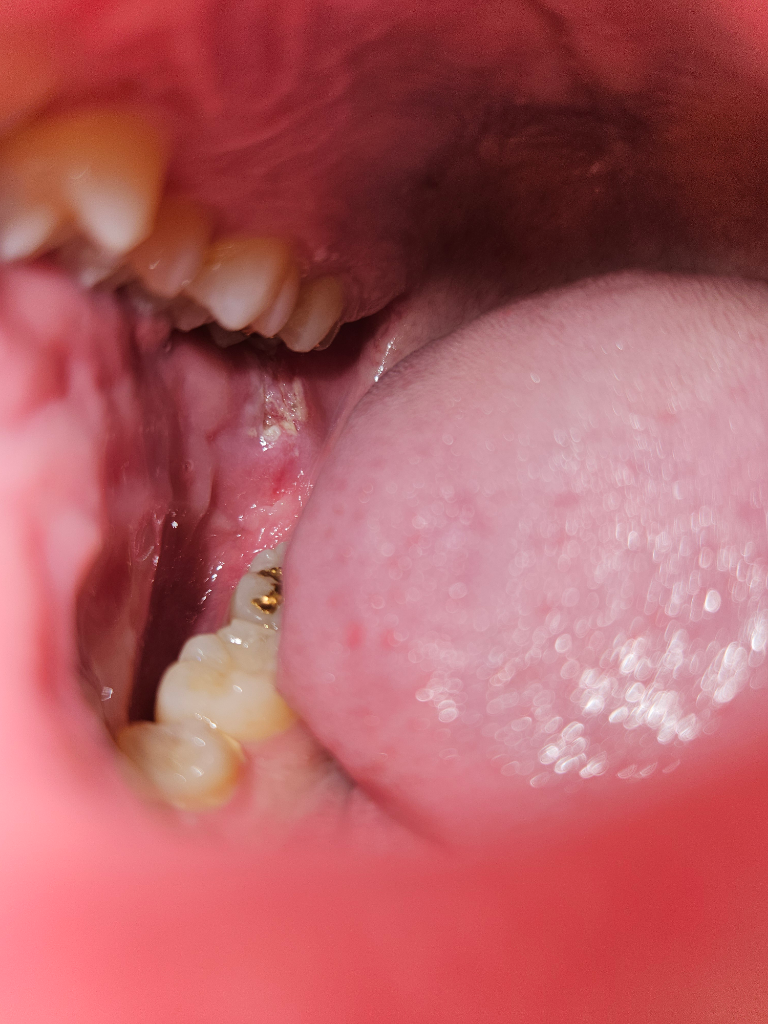

현재 치아 교정 중입니다. 두 달 전 식사를 하던 중 교정기 철사가 왼쪽 볼을 찌르며 볼살에 낀적이 있는데 그때는 상처가 없었던것같고 후에 치과 방문 후 철사가 볼을 찌르지 않도록 조치 하였습니다. 그 후 따로 아픈적은 없었던거같은데 대략 2주 전 그때 찔렸던 왼쪽 볼에 상처가 났으며 상처 부위에 음식을 씹으며 치아가 닿거나 양치를 하는 등 무언가 닿게 되면 아프고 무언가 닿지 않으면 별 다른 느낌이 없습니다. 그냥 단순히 교정기가 쓸려 난 상처인가요? 아니면 다른 병이나 그런게 있는 건가요 병원은 이번주 방문이 힘들어 다음주 토요일 27일에 치과 방문이 예약되어 있어 그때 방문할까 합니다.아래 사진 첨부합니다.

입안에 염증이 생긴 것으로 보이며, 이 경우 소독을 위해 헥사메딘 가글액으로 가글하고, 구내염 연고 사용을 하며 상태를 지켜보길 권합니다.

양상은 외상성궤양이고 위치상 교정 철사의 찔림으로 그런것 같습니다 구강내 적용가능한 연고를 바르면 도움이 됩니다